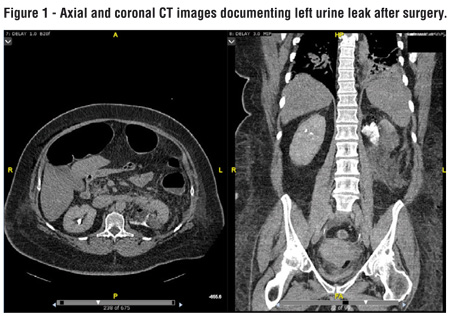

Clinically significant urine leak was defined as persistent drain output >48 hours after PN with biochemical analysis consistent with urine or radiographic evidence of urine leak (15). Radiological imaging was only performed where patient’s clinical status or symptoms were suggestive of urine leak (Figure-1).